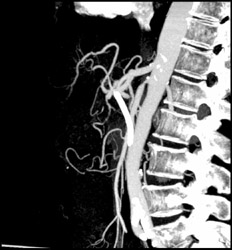

Pancreatic Mass With Incidental Endoleak